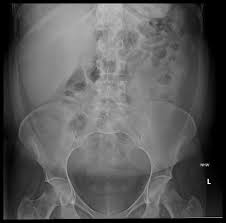

- Abdominal X-ray, a noninvasive X-ray study to evaluate abdominal organs.